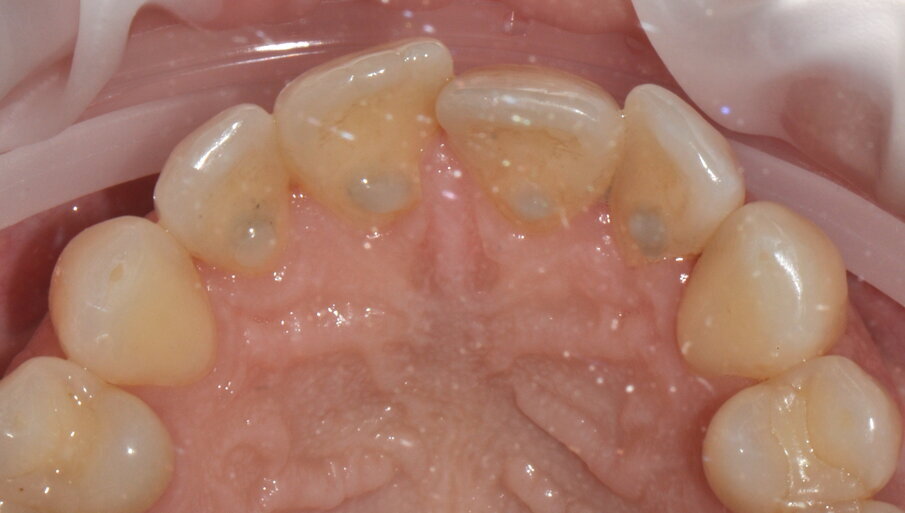

- Applicazione del rilevatore di placca bifasico: permette la distinzione fra i depositi di placca recenti da quelli meno recenti ( 1a-1c);

Figg. 1a-1c - Applicazione del rilevatore di placca che verrà usato come guida durante la terapia, nel versante vestibolare (1a), palatale (1b) e linguale (1c). Si noti lo scarso livello di igiene orale domiciliare e l’assenza di utilizzo dei presidi interdentali.